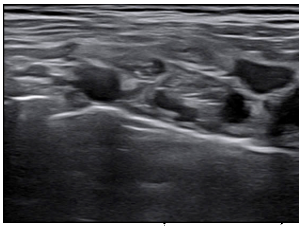

- Siêu âm hạch cổ: hạch bất thường thượng đòn 2 bên kích thước 8x15mm; không rõ cấu trúc rốn hạch

- Sinh thiết hạch thượng đòn phải dưới hướng dẫn của siêu âm cho kết quả:

Giải phẫu bệnh: Ung thư biểu mô di căn hạch

Hóa mô miễn dịch: Hình hình ảnh mô bệnh học và hóa mô miễn dịch phù hợp với ung thư biểu mô tuyến phổi di căn hạch; PDL-1 dương tính, TPS= 95%; EGFR (-); ALK (-)

- Siêu âm hạch cổ: không phát hiện bất thường

Hình 9: Hình ảnh siêu âm hạch cổ: không phát hiện bất thường